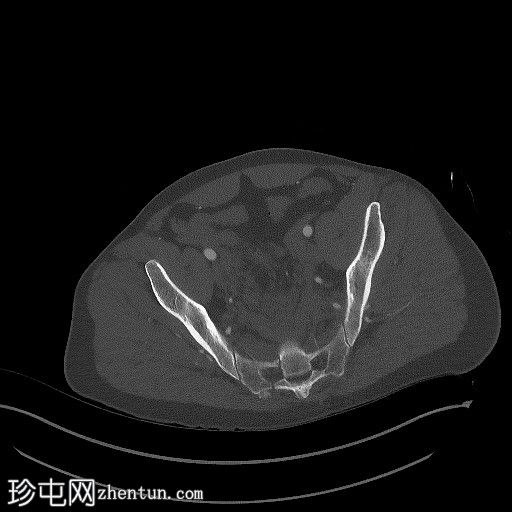

X光片

骨盆固定带在位。左侧耻骨上支和下支轻微移位骨折。髋臼正常。左侧髂骨翼斜形骨折(新月形骨折)延伸至左侧骶髂关节。骶髂关节未见增宽。耻骨联合未见增宽。右侧骶骨在骶髂关节下方骨折。尾骨向左侧脱位。